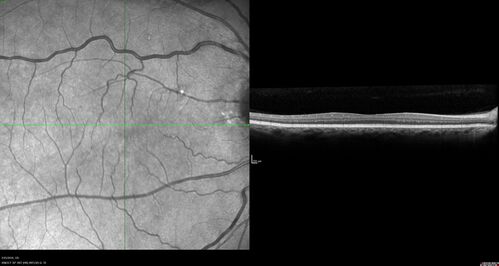

Amelanotic Choroidal Nevus - Multimodal Imaging

61 year old man with amelanotic choroidal nevus. Vision Normal - Stable over 4 years.